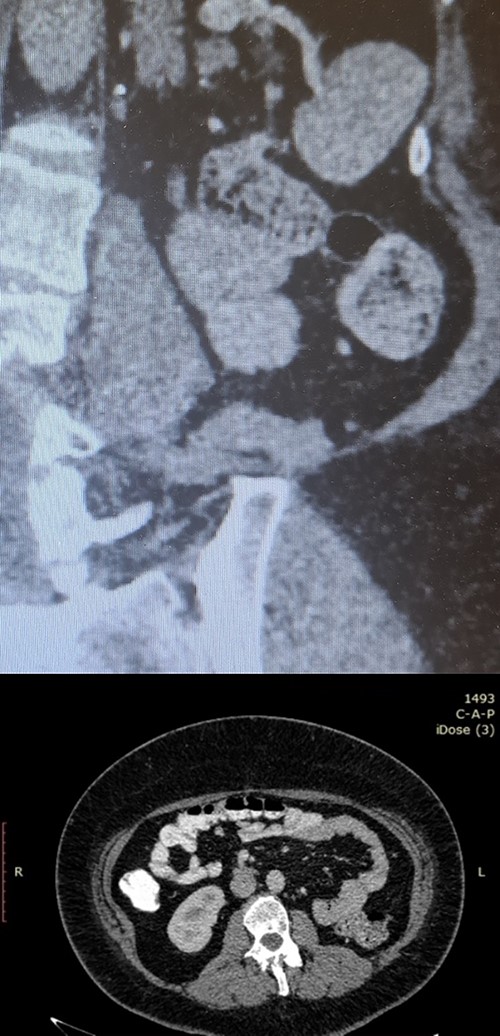

A 20-year-old Caucasian woman presented herself to the outpatient department because of a mass on the left kidney. The mass was an incidental finding in an abdomen computed tomography (CT), which was suggested within the diagnostic evaluation for a persistent flank pain. In the past, she never had any pathologic urologic situation. According to the CT finding, the mass was located on the lower pole of the left kidney (83 × 111 × 111mm) and there was no other pathologic finding. Anamnestically, she had heterozygous beta Mediterranean anaemia. The patient was obese (body mass index = 33.4 kg/m2). We proceeded with a thorax CT which revealed no pathology. The patient underwent a laparoscopic nephrectomy by an urologist well trained and experienced in laparoscopy. Macroscopically, a mass in the lower pole of the left kidney (110 × 100 × 100 mm) was documented. Cut sections revealed multiple thin walled, non-communicating cysts of varying sizes with smooth lining without solid component. Microscopically, the tumor was characterized of cysts separated by thin septa. The cysts lined by single layer of flat, cuboidal and hobnail epithelium and the septa were fibrous, hypocellular to hypercellular. No mitoses or necrosis were identified. The immunohistochemical examination showed that the epithelial cells were positive for the cytokeratins AE1/AE3 and PAX-8. The stromal cells were positive for the progesterone receptors, estrogen receptors and CD10. The latter was concentrated around epithelial elements (Figs 1 and 2). These findings established the diagnosis of ACN. At the 12-month follow-up control with abdomen CT, there was no pathologic finding (Fig. 3). The patient is under urologic and nephrologic montitoring without any abnormal finding at 21 months after surgery. This research complies with the guidelines for human studies and was conducted ethically in accordance with the World Medical Association Declaration of Helsinki.

Postoperative follow-up imaging with abdomen CT at 12 months; coronal (upper side) and axial (lower side) planes, and no evidence of local recurrence, and no other pathologic finding.